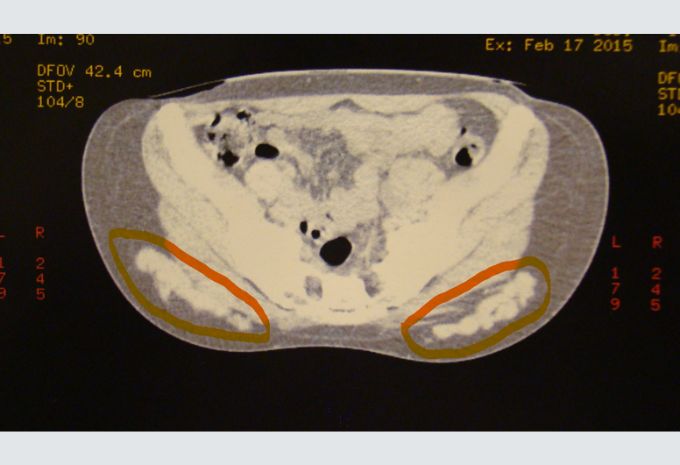

En las fotos se muestran granulomas con PMMA extraídos a paciente a la cual se la salvó de una posible insuficiencia renal y litiasis renal a repetición. En la imagen de la tomografía axial computada preoperatoria de la paciente se observa (ver círculos naranjas) la enorme cantidad de PMMA que tenía en su cuerpo.

Imagen de tomografía axial computada preoperatoria de paciente a la cual se le extrajo esa enorme cantidad de PMMA (ver círculos naranjas)